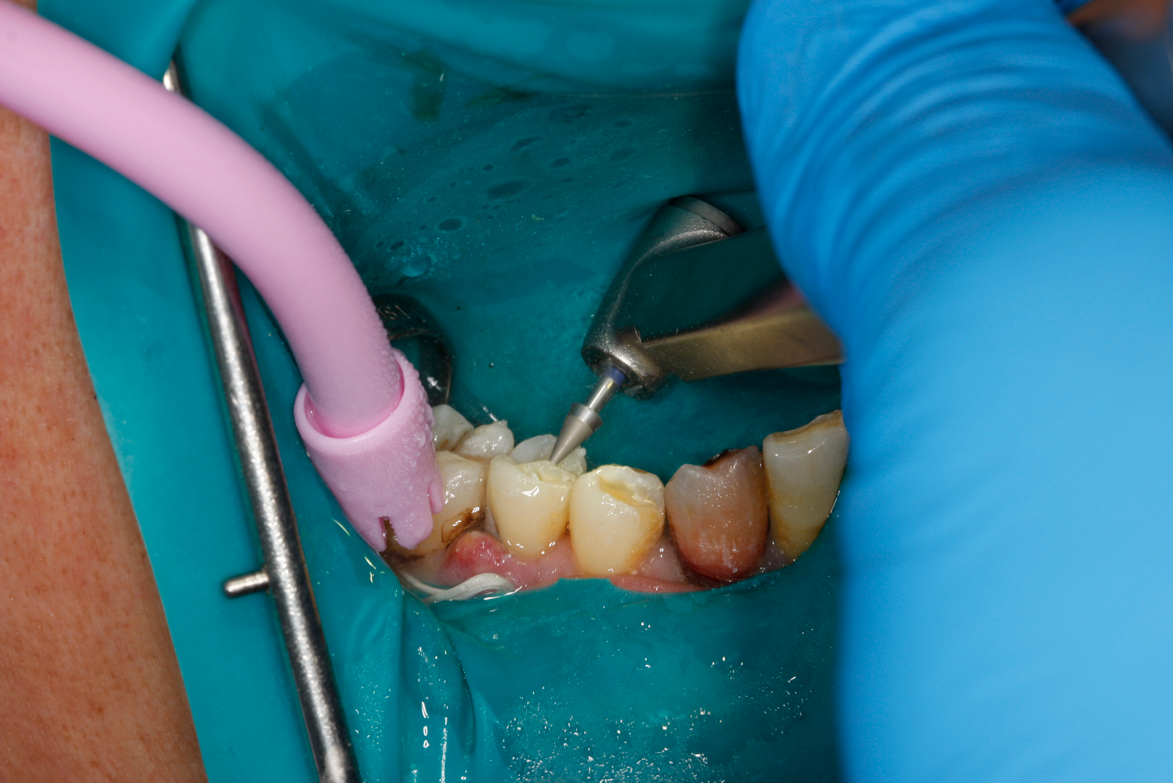

Figure 8A is a radiograph revealing deep root caries previously restored temporarily by a resident at the AEGD Residency Program clinic with glass ionomer utilizing a lateral rather than occlusal approach. After the glass ionomer failed to adhere, another resident again attempted a lateral approach that resulted in the restoration shown in Figure 8B. A third resident had success with an occlusal approach, removing a failed occlusal composite to access the distal  (Figure 9). This attempt was successful both in the preparation of the lesion and in the placement of a dual- cure bulk-fill flowable (Bulk EZ Plus, Zest Dental Solutions; alternatively: HyperFIL®, Parkell; Fill-Up!, Coltene) extruded through a bendable needle (Figure 10). Figure 11 shows the final preparation after tissue removal was accomplished with rotary gingitage; note that this was performed with the rubber dam in place. An air abrasion device (Groman Etchmaster, Groman Dental; alternatively: PrepStart H2O, Zest Dental Solutions; Bioclear Blaster, Bioclear) was used with potassium bicarbonate to remove biofilm prior to acid etching (Figure 12). Phosphoric acid 37% was utilized in a total etch fashion (Fig- ure 13 and Figure 14) for 20 seconds. Figure 15 shows the universal bond (Scotchbond Universal, 3M; alternatively: All-Bond Universal®, BISCO; Prelude One, Danville Materials) with metha- cryloyloxydecyl dihydrogen phosphate (MDP) being scrubbed into the cavity for 20 seconds. After air thinning for 20 seconds, the adhesive was light cured for 40 seconds at 1,200 mw/cm2power density (Figure 16).

Fig 10. Occlusal approach was successful in the placement of a dual-cured bulk-fill flowable. Note the depth of box form.

Figure 10

Fig 11. Final preparation after gingitage with coarse diamond bur to remove soft tissue from the cavity in tooth No. 2.

Figure 11

Fig 12. Utilizing particle blasting with a microetcher loaded with potassium carbonate to remove biofilm in the cavity and margins.

Figure 12

Fig 13. Total etch with 37% phosphoric acid.

Figure 13

Fig 14. Cavity preparation flooded with phosphoric acid in total etch.

Figure 14

Fig 15. Universal bond is scrubbed into dentin for 20 seconds, applied to the enamel, and air-thinned.

Figure 15

Fig 16. Adhesive was light-cured for 40 seconds due to the depth of the box preparation.

Figure 16